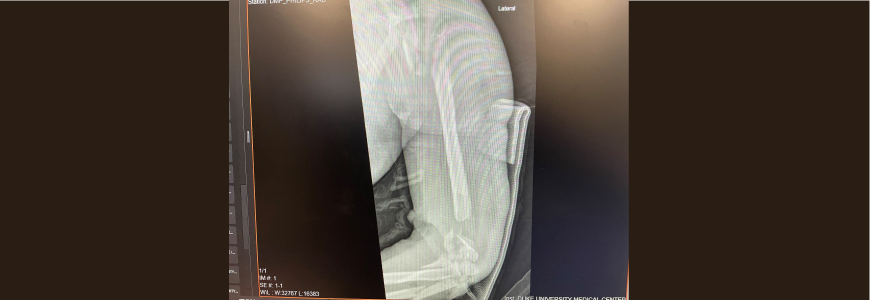

Radiograph of elbow graft

After a 2021 rollover accident in an all-terrain vehicle, a woman in her 30s sustained damage to her internal organs as well as proximal and midshaft fractures of the left humerus. The upper extremity fractures involved ulnar nerve injury, proximal forearm injury, and circumferential soft tissue laceration to the bone.

“This was one of the worst elbow injuries I’ve treated,” says Duke Health orthopaedic surgeon David S. Ruch, MD, chief of the hand, wrist, and upper extremity division. “She was missing 4 inches of the bone into the elbow. Realistically, she was a candidate for amputation in the midshaft humerus.”

Ruch used an innovative graft technique to rebuild the patient’s humerus through multiple surgeries. After stabilizing the arm, Ruch installed a long plate to hold the upper arm to length using a bone cement spacer infused with antibiotics. The spacer helped to create a membrane conducive to integrating a subsequent bone graft.

Approximately six weeks later, Ruch and team removed the cement spacer to place an autologous bone graft from the patient’s femur. “You can only obtain such a massive amount of bone from the femur,” says Ruch. Orthopaedic trauma surgeon Malcolm DeBaun, MD, assisted with obtaining the graft.

With the original long plate holding the elbow at 90 degrees, the team installed additional plates on either side of the bone to stabilize the arm while the graft incorporated into the humerus as well as the extant bone fragments in the elbow. To preserve function and sensation, “we also transposed the ulnar nerve out of the way of the injury, and the nerve was able to recover,” Ruch adds.

After the graft healed, Ruch removed the long plate. Through occupational therapy, the patient was able to regain 60 degrees of motion in her elbow and retain the use of her hand, now two years postsurgery. “It’s a million percent better than it was,” the patient says. “I am so grateful just to have an arm, and it works great.”